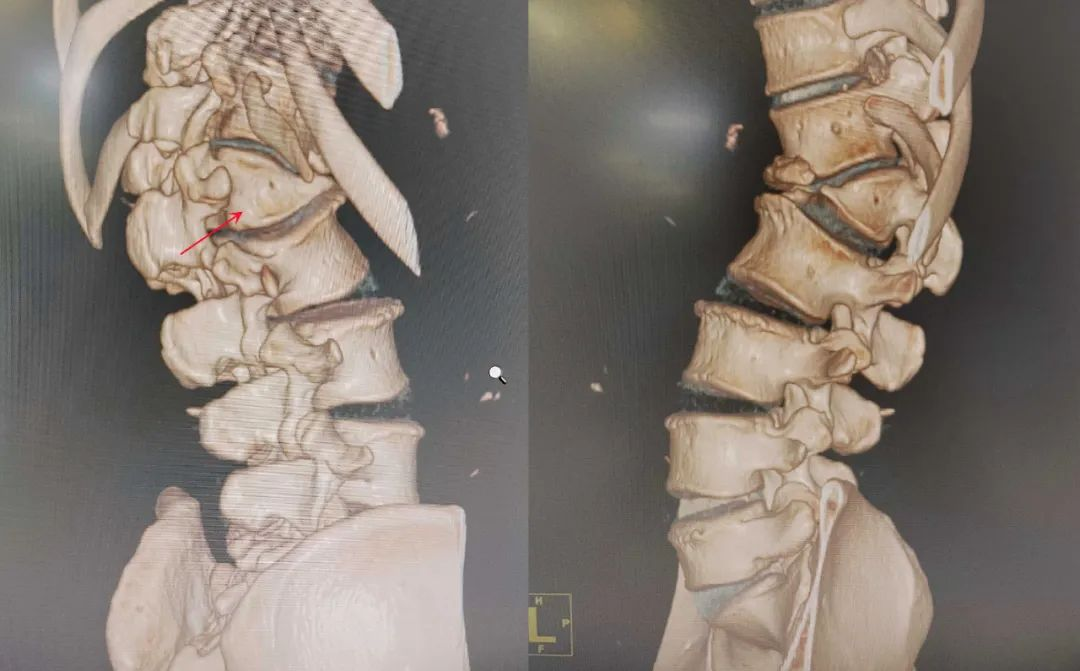

▲CT三维重建示:腰1椎体半椎体畸形